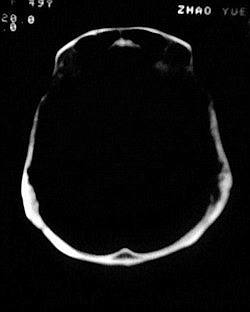

患者/49y/ 女/4年前有脑梗, 现因右侧肢体无力来院做ct扫描 ! 老师们看看这骨头有事吗?钙化点是什么原因呀??

1.颅骨对称性、形态规整性增厚,应属发育异常。四叠体池左后侧单发点状钙化,无其他阳性表现,多属正常,不需要过多关注。

2、颅骨形态规整性的增厚,密度增高,有无骨髓方面的疾病,建议骨髓穿刺。

可能为颅骨内板增生症,以额骨多见,常见于女性.多无临床意义.部分病人可有头痛.可找相关资料看看.

2.颅骨内外板广泛性增厚,板障狭窄甚至消失,双侧对称。无明显相应临床症状。考虑“泛发性骨皮质增厚症”。可进一步检查下颌骨及管状骨骨干。(下颌骨骨小梁增多、密集,密度增高亦为本病特点,管状骨骨干皮质向内增厚引起骨皮质厚度增加,骨密度增浓、髓腔狭窄但不消失,骨干周径较少增加)。与石骨症鉴别,后者很少影响颅盖骨和下颌骨,管状骨改变主要累及干骺端和骨骺,而骨干皮质较少增厚,椎体和髂骨翼有特征性表现。